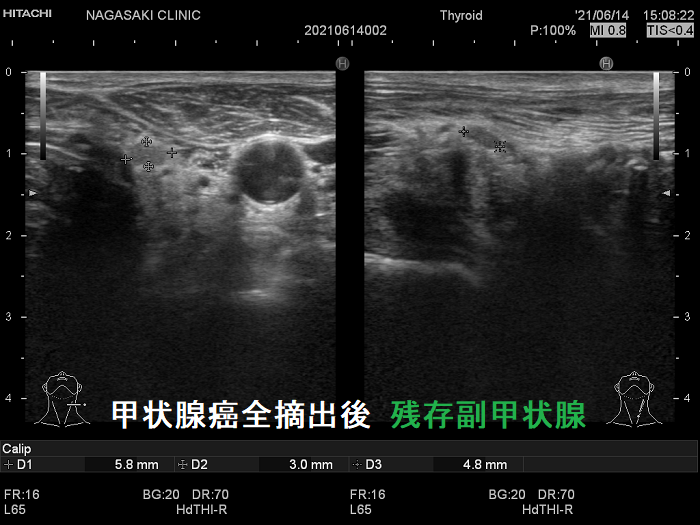

- 甲状腺摘術後、TSH 抑制療法;バセドウ病/甲状腺腫瘍で甲状腺切除と同時に副甲状腺も取ってしまった場合、取らずに温存した場合でも副甲状腺への血管を傷つけた場合

- 甲状腺全摘術時、副甲状腺も1-4腺を同時切除、あるいは切除しなくても栄養血管を損傷

- 術後副甲状腺機能低下症による低カルシウム血症;術直後のみならず、10年~30年以上して著明な低カルシウム血症で発症する事もある(日腎会誌 2012;54(1):40-47.)(J Clin Diagn Res. 2017 Feb; 11(2): OD07–OD09.)。

ケース①

ケース②